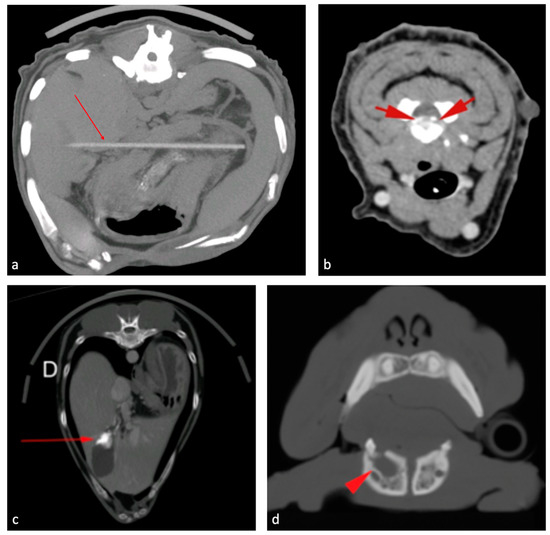

Figure 1.

Examples of incidentalomas found in the CT examinations. (a) Peritoneal foreign body (arrow); (b) intervertebral C3/C4 disc herniation (arrows); (c) cholelithiasis (arrow); (d) mandibular cyst (arrow tip).